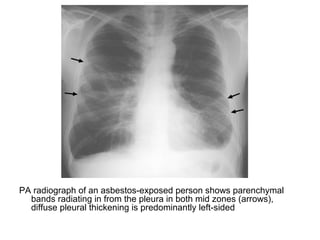

PA radiograph of an asbestos-exposed person shows parenchymal

bands radiating in from the pleura in both mid zones (arrows),

diffuse pleural thickening is predominantly left-sided